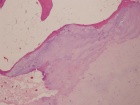

68 yo male with complaints of right shoulder pain with repetitive activities and modified with rest. History of multiple orthopaedic surgeries in the past. He denies history of trauma or constitutional symptoms.

PE: Elderly male in good overall health. Short stature. Palpable mass in posterior right shoulder. Nontender w/o edema or overlying skin changes. Limited ROM in all dimensions. NVI w/o LAN.